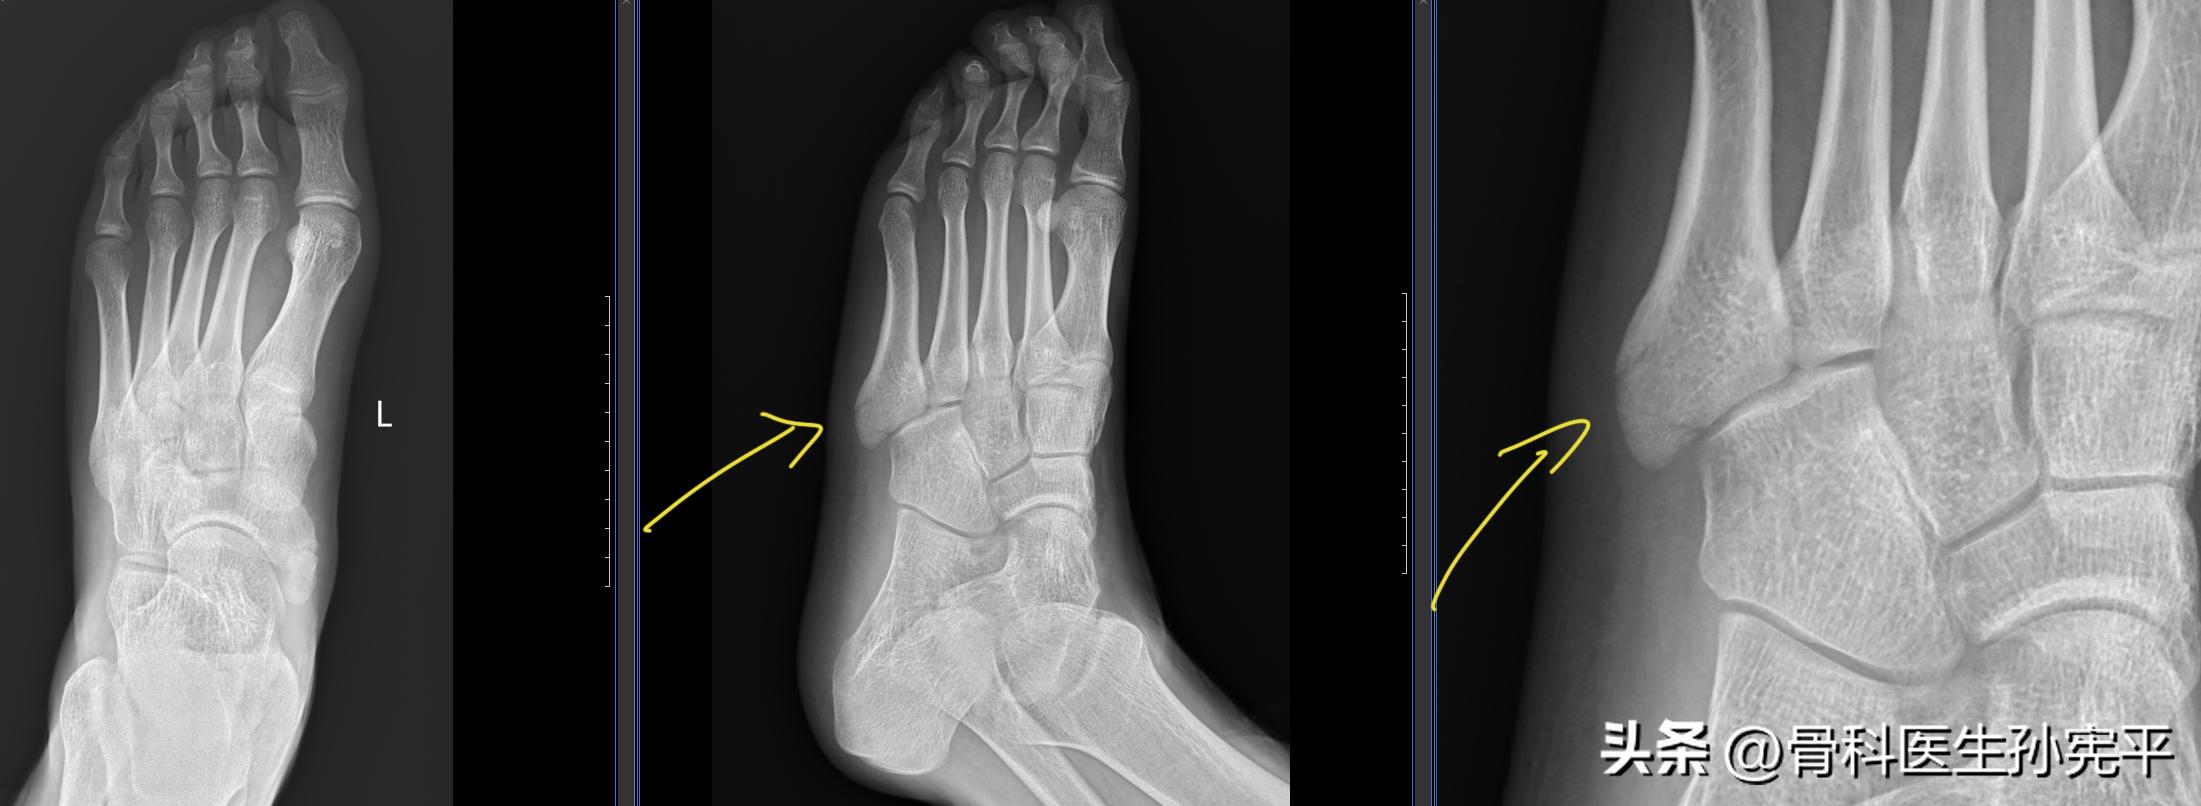

病例8:扭伤后左足疼痛2小时。

左足第5跖骨基底骨折

阅片可见左足第5跖骨基底骨质结构断裂,对位尚可。